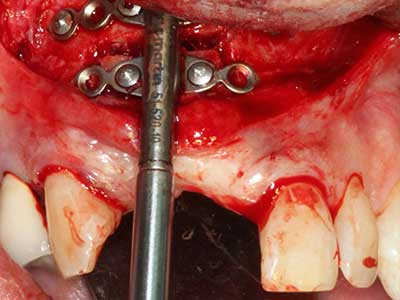

El tejido óseo no solo tiene un contenido puramente mineral, sino que también presenta una importante proporción de fibras de colágeno. Esto no solo garantiza una buena resistencia a la presión, sino también una cierta flexibilidad, que puede aprovecharse para la realización de aumentos. En la plastia de expansión clásica a efectos de una partición ósea, la cresta maxilar atrofiada se divide en su eje longitudinal y, tras alcanzar una profundidad de osteotomía suficiente, se extiende con cuidado (fig. 13-16), en un caso ideal sin desperiostizar de forma visible el maxilar (Brugnami, Caiazzo et al. 2014, Stricker, Fleiner et al. 2014). Los sistemas de tornillos y placas con distancia de expansión creciente han demostrado su eficacia para distanciar entre sí las dos tablas óseas por debajo del umbral de rotura. Por regla general, se requieren anchuras de hueso residual de al menos 3 a 4 mm (Chiapasco, Zaniboni et al. 2006) para garantizar una flexibilidad y una cobertura ósea suficientes de los implantes que van a incorporarse. En caso necesario, una osteotomía de descarga vertical unilateral o bilateral puede mejorar la flexibilidad. Como alternativa a la técnica clásica se ha descrito una combinación con otras técnicas de aumento, sobre todo en la parte bucal.

Con el uso de sierras piezoeléctricas la división se efectúa de forma especialmente cuidadosa y sin pérdidas importantes de las dimensiones, por lo que no se han encontrado diferencias significativas entre los implantes realizados en el maxilar dividido y en la cresta alveolar no deficitaria (Chiapasco, Zaniboni et al. 2006, Danza, Guidi et al. 2009). No obstante, precisamente en la partición profunda y limitada de forma local, es preciso asegurarse de que exista una adecuada irrigación por agua para evitar que se produzcan sobrecargas térmicas en las áreas de osteotomía apical.